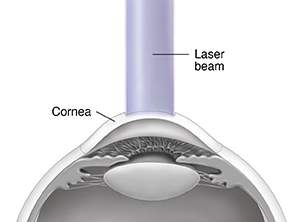

PRK (photorefractive keratectomy) is a procedure to reshape the cornea. It may help you see better without glasses or corrective lenses. This method uses an excimer laser. This laser makes a concentrated beam of ultraviolet (UV) light. Each pulse of the laser can remove a tiny part of the cornea. PRK can be used to treat the following:

A small surgical tool, an alcohol solution, or the laser is used to remove the surface of the central part of your cornea (the epithelium). Laser treatment lasts for 10 to 90 seconds.